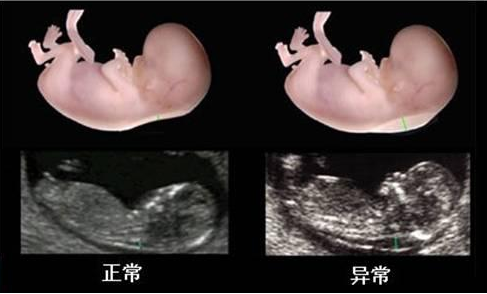

做NT檢查對胎兒有影響嗎?NT檢查是孕期一項胎兒排畸檢查,是篩查只能評估寶寶患有唐氏綜合癥的風險的一種檢查,那么,NT檢查異常怎么辦?接下來八寶網小編就來說一說。

NT檢查是B超檢查的一種,而且是在孕早期檢查,很多準媽媽擔心會對胎兒造成不良影響。

但其實,經過有關專家的長期實驗,并沒有發現做NT檢查會對胎兒有不良的影響,恰恰相反,是早期發現胎兒異常的一種有效的影像學方法,對于產前篩查高風險的孕婦是否需要進一步抽羊水檢查具有指導意義,所以準媽媽們大可放心。